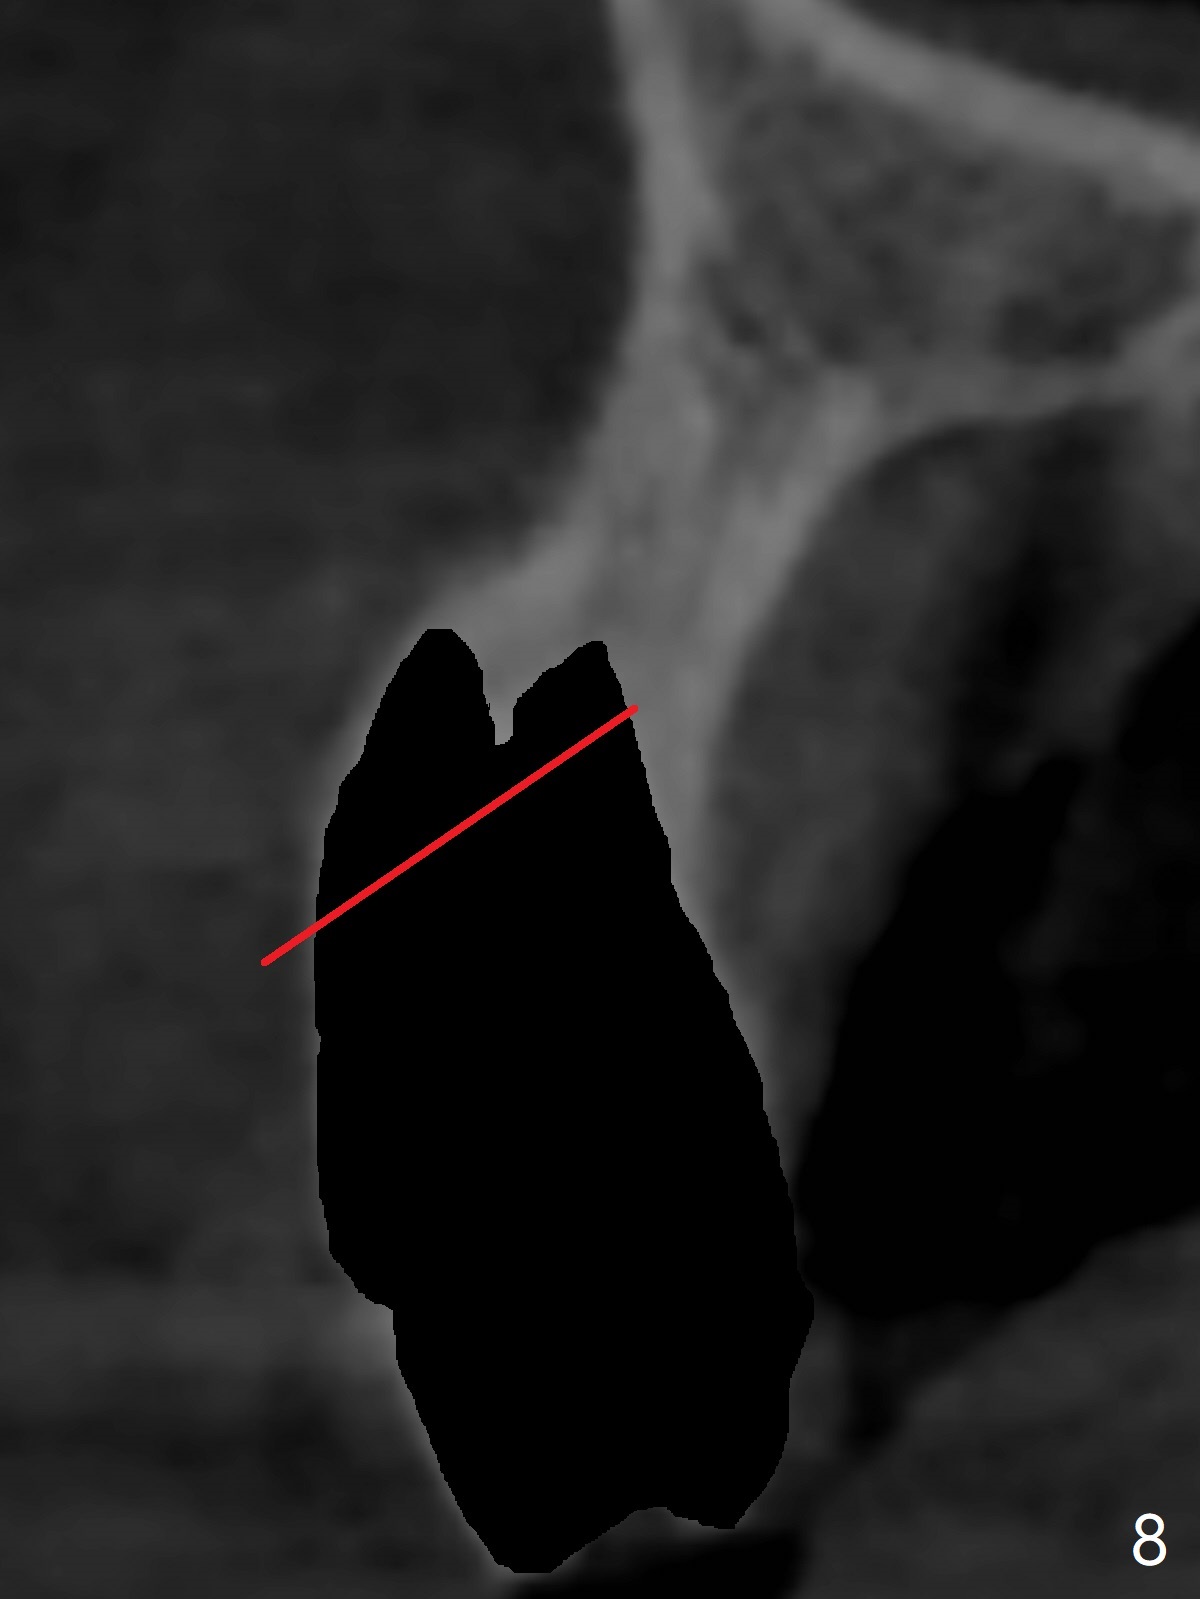

A 51-year-old woman lost the teeth #6 and 7 due to odontoma removal ~30 years ago. The area was restored with a FPD. The latter is removed with immediate implant at #8 8-9 months earlier. Particulate bone graft does not repair the bone deficiency at #6, 7 (Fig.2,3), although the soft tissue looks bulky (Fig.1). It appears that the palatal defect also needs a piece of bone block to fill in (Fig.4). The block will be harvested from the chin (Fig.5,6). If the block graft turns out to be impracticable, the periodontally compromised tooth #5 (bone loss, Fig.2,3,7) will be extracted for immediate implant. Initial osteotomy will be established in the palatal socket (Fig.8,9). Either a 2- (Fig.10) or 1- (Fig.11) piece implant will be placed. After wound healing, impression will be taken for a lab-fabricated provisional FPD.